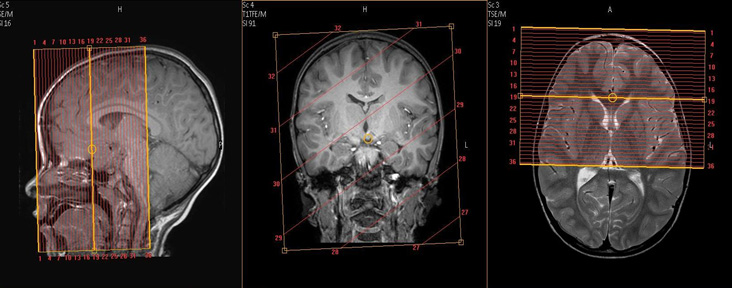

MR Orbits WO Neuro Protocol

Coronal orbits coverage: Anterior margin of globe to anterior surface of pons, perpendicular to axis of the orbital segment of the optic nerves.

Axial orbits coverage: Superior margin of orbital rim to inferior margin of orbital rim, angled to be in-plane with the orbital segments of the optic nerves.